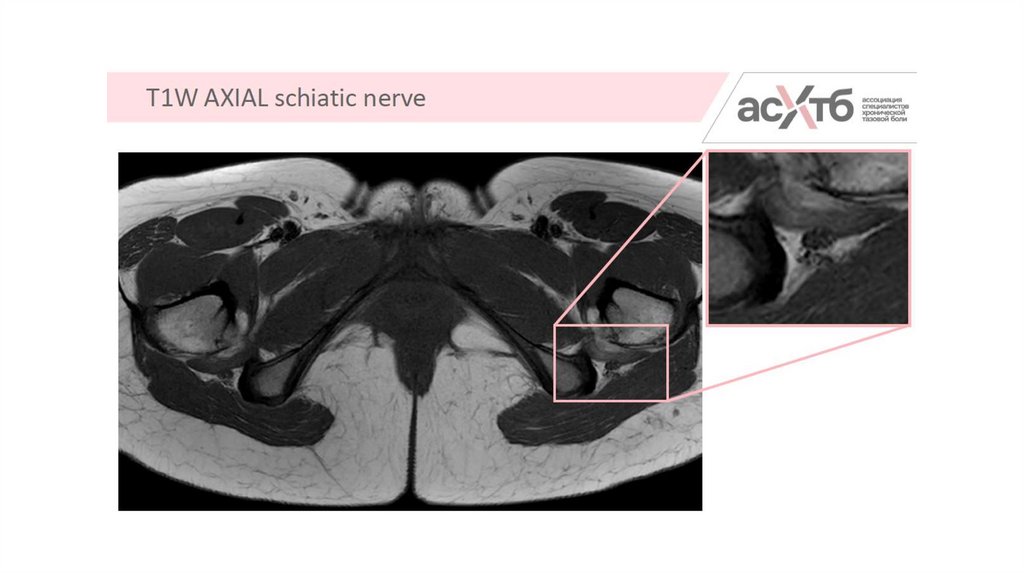

8. Режимы

17. Как должен выглядеть нерв в норме

18. Признаки патологии